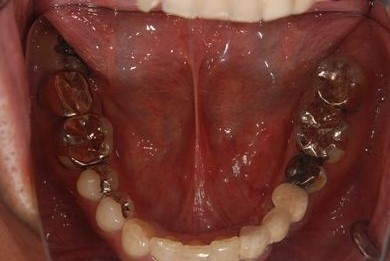

| 性別/年齢 | 男性 / 46歳 | ||||||||||||||||||||||||||||||||

| 治療内容 | インプラント2本(抜歯即日スピードインプラント)、ハイブリッドセラミック2本 | ||||||||||||||||||||||||||||||||

| 総治療費 | 456,750円 | ||||||||||||||||||||||||||||||||

| 治療期間 | 7ヶ月 |